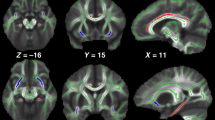

We provide an effect-size map of the group differences in cortical gray matter volume to give the reader an impression of the anatomical distribution of group differences across a range of P values uncorrected for multiple comparisons. This effect-size map may be used for comparison with findings of future studies as well as with hypothesis generation. To generate the effect-size map, we performed group comparisons at each vertex of the extracted cortical surfaces using QDEC (Query, Design, Estimate, and Contrast) within FreeSurfer, while controlling for age and gender. In the resulting effect-size map, differences are visualized using blue colors to indicate regions, where patients had lower cortical gray matter volume relative to controls, and red colors to indicate regions, where patients had higher cortical gray matter volume relative to controls.

The surface-based effect-size map of group differences in cortical gray matter volume, controlling for age and gender, showed widespread cortical areas with smaller volume in patients relative to controls with no apparent anatomical predilection (Supplementary Figure S1 online).